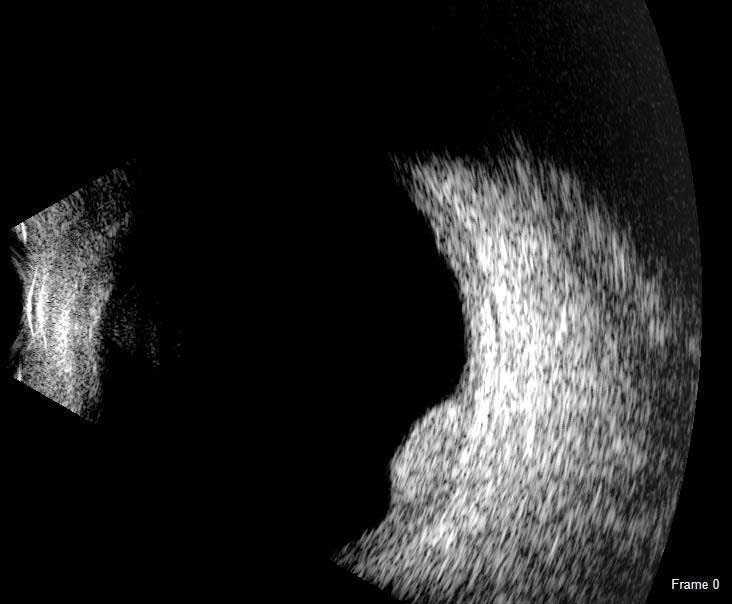

B-Scan: Перероблений зонд B-Scan, новий для Flex, забезпечує чітке зображення заднього відрізка ока, навіть якщо оптична чіткість порушена.

B-Scan

Датчик Scanmate Flex B-Scan дозволяє лікарям отримувати чіткі і точні зображення і відеозаписи заднього відрізка ока. Ультразвукове В-сканування ефективне навіть при наявності помутнінь (таких як щільна катаракта, кров або анатомічні структури), які заважають оптичним технологіям.

Зонд B-Scan доступний з частотами 12,5 МГц і 20 МГц. Серед екранних інструментів є штангенциркуль для вимірювання структур, інструмент для вимірювання площі та інструмент анотації, який дає змогу позначити патології на зображенні.

B-Scan може допомогти в оцінці: Відшарування сітківки або склистого тіла;

Патологій гуморальної оболонки склистого тіла стафіломи, заднього сегмента, судинної оболонки, зорового нерва або потовщення склери.